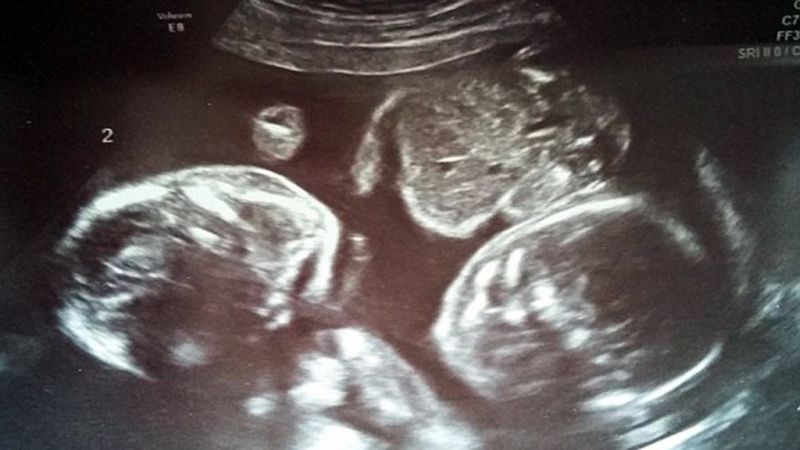

Sin embargo, lo que los padres pudieron ver a través de las ecografías fue precisamente lo contrario. No sólo estaban quietos, sino que parecían cuidar el uno del otro.

"A mí marido y a mí nos rompió el corazón saber que estaban en peligro. Necesitaban mantenerse quietos para sobrevivir, pero en algunas imágenes parecía que se estuviesen acurrucando el uno contra el otro. Incluso teníamos la impresión de que se daban la mano", recuerda emocionada la madre.